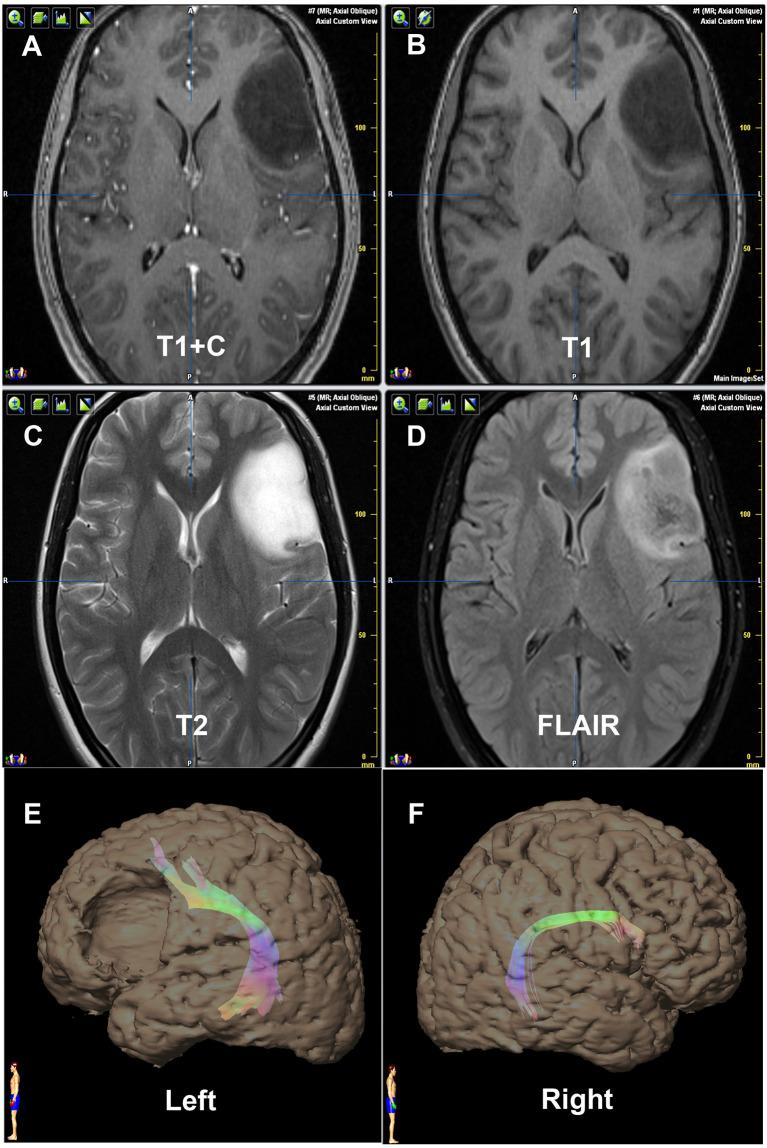

Language lateralization is unique to humans, so clarifying dominant side is helpful for removing gliomas involving language areas. This study investigated the arcuate fasciculus (AF) reconstructed by diffusion tensor imaging-based tractography (DTT) in predicting language lateralization in patients with low-grade gliomas. Wada test was performed to determine the language Dominant Hemisphere (DH) and the Contralateral Hemisphere. DTI data [1.5-T magnetic resonance imaging (MRI)] was used to reconstruct AF by two independent operators using a DTT method. Fiber number, volume, and fractional anisotropy (FA) of bilateral reconstructed AF were measured. Lateralization indexes (LIs), including Number Index (NI), Volume Index (VI), and FA Index (FI), were accordingly calculated by mean values. A total of 21 patients with WHO Grade II gliomas in the left hemisphere were included. Every patient received a successful Wada test and reconstruction of bilateral AF. DTT metrics of reconstructed AF, such as fiber number, volume, and FA, showed significantly asymmetric between hemispheres. All the LI (NI, VI, and FI) values were statistically higher in the DH determined by the Wada test. No discrepancy was found between the prediction using the cutoff values of DTT metrics and the results of WADA test. The Kappa values were 0.829, 0.696, and 0.611, indicating NI and VI as more reliable predictor than FI although FI itself may also be feasible. Compared with the Wada test, we consider that DTT of AF is a non-invasive, simple, relatively accurate, and feasible method in predicting language lateralization in patients with low-grade gliomas.

语言侧化是人类独有的,因此明确优势侧有助于切除累及语言区的胶质瘤。本研究调查了基于扩散张量成像纤维束示踪(DTT)重建的弓状束(AF)在预测低级别胶质瘤患者语言侧化中的作用。进行Wada试验以确定语言优势半球(DH)和对侧半球。使用1.5-T磁共振成像(MRI)的DTI数据由两名独立操作人员采用DTT方法重建AF。测量双侧重建AF的纤维数量、体积和分数各向异性(FA)。相应地通过平均值计算包括数量指数(NI)、体积指数(VI)和FA指数(FI)在内的侧化指数(LI)。共纳入21例左半球WHO二级胶质瘤患者。每位患者均成功进行了Wada试验和双侧AF重建。重建AF的DTT指标,如纤维数量、体积和FA,在半球间显示出明显的不对称性。在Wada试验确定的DH中,所有LI(NI、VI和FI)值在统计学上更高。使用DTT指标的临界值进行的预测与WADA试验结果之间未发现差异。Kappa值分别为0.829、0.696和0.611,表明NI和VI比FI是更可靠的预测指标,尽管FI本身也可能可行。与Wada试验相比,我们认为AF的DTT是一种预测低级别胶质瘤患者语言侧化的非侵入性、简单、相对准确且可行的方法。